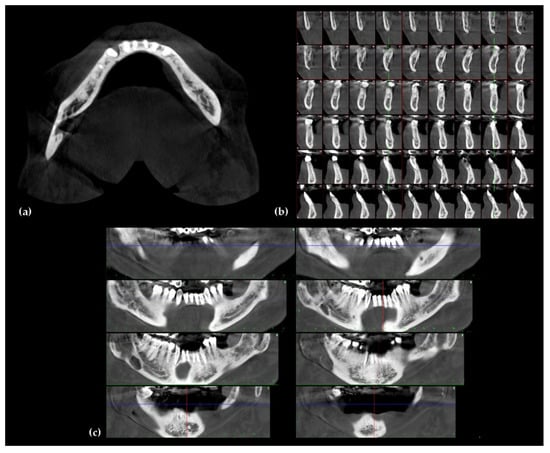

4. Imaging